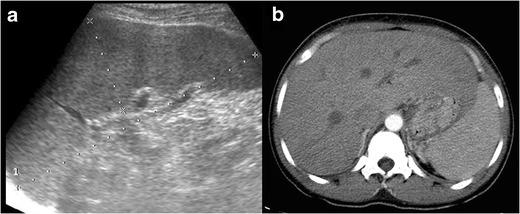

Radiologists seldom encounter parasitic diseases in their daily practice in most of Europe, although the incidence of these diseases is increasing due to migration and tourism from/to endemic areas. Moreover, some parasitic diseases are still endemic in certain European regions, and immunocompromised individuals also pose a higher risk of developing these conditions. This article reviews and summarises the imaging findings of some of the most important and frequent human parasitic diseases, including information about the parasite's life cycle, pathophysiology, clinical findings, diagnosis, and treatment. We include malaria, amoebiasis, toxoplasmosis, trypanosomiasis, leishmaniasis, echinococcosis, cysticercosis, clonorchiasis, schistosomiasis, fascioliasis, ascariasis, anisakiasis, dracunculiasis, and strongyloidiasis. The aim of this review is to help radiologists when dealing with these diseases or in cases where they are suspected. Teaching Points • Incidence of parasitic diseases is increasing due to migratory movements and travelling. • Some parasitic diseases are still endemic in certain regions in Europe. • Parasitic diseases can have complex life cycles often involving different hosts. • Prompt diagnosis and treatment is essential for patient management in parasitic diseases. • Radiologists should be able to recognise and suspect the most relevant parasitic diseases.